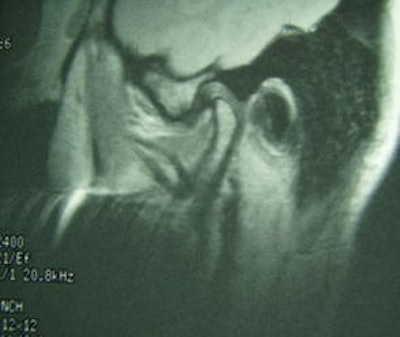

![]() |

Fifty-year-old woman with clicking and pain in both TMJs, 8-mm mandibular advancement, and MIO that decreased from 42 mm to 40 mm postoperative. Above, bilateral, right anterior disk displacement on MRI preoperative, which did not change on postoperative MRI, below. Images courtesy of Dr. Jessica Lee.